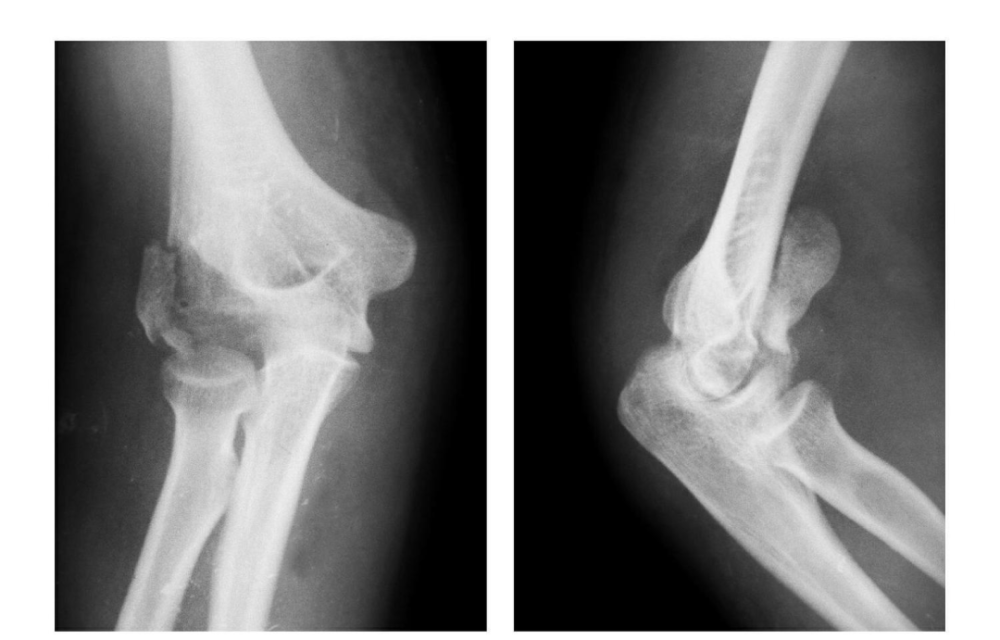

影像基础 肘关节骨折的影像学诊断及分型 移位